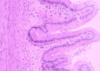

Small intestine - muscularis externa, intestinal glands, submucosa, muscularis mucosa, intestinal villi

Microvilli of the Duodenum - microvilli (curved arrows) of the duodenum. Each microvillus is covered with the plasma membrane which has an external glycocalyx of glycoproteins some of which function as enzymes that participate in the terminal digestion of proteins and carbohydrated. The central core of the microvilli is occupied by actin microfilaments and several actin binding proteins. Microfilaments from the microvilli extend into the apical cytoplasm to from part of the terminal web (TW).